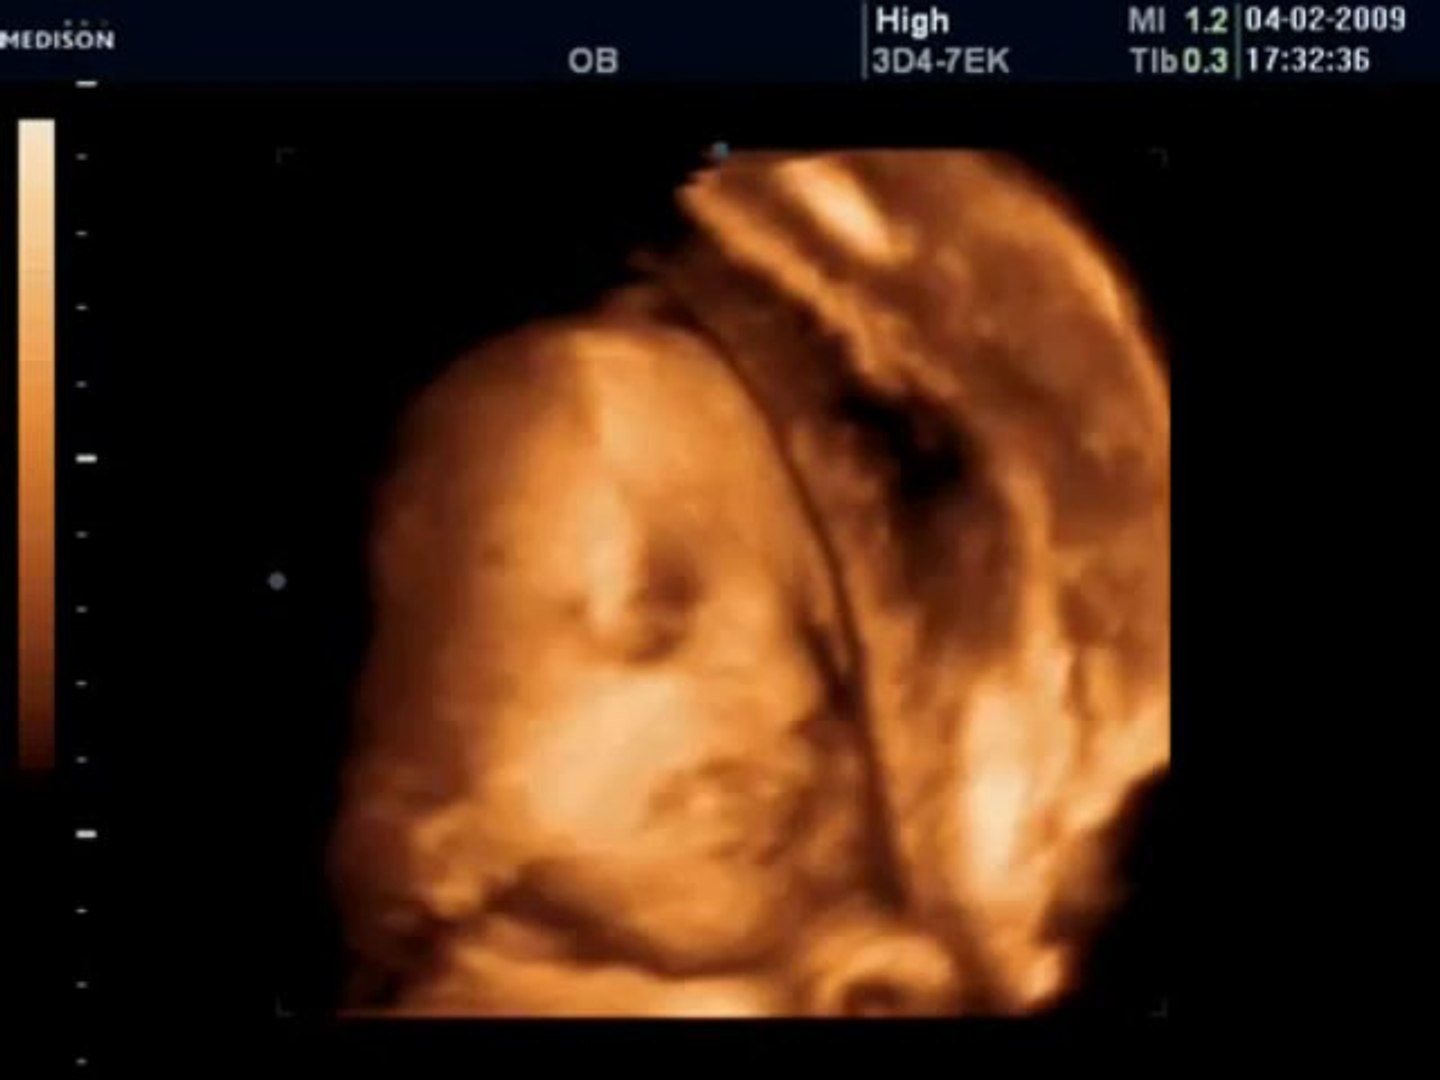

29 Haftalık Gebelik Bebek Hareketleri

29 Haftalık Gebelik Bebek Hareketleri.

29 hafta gebelik